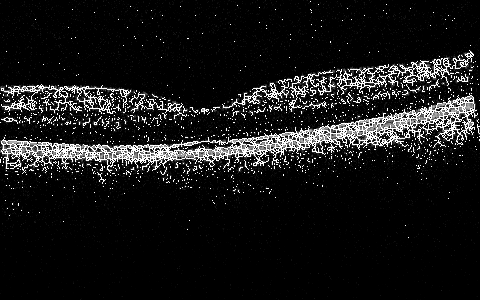

Sun et al. covered various aspects of the OCT image processing and classification using earth mover distance, SVMs, providing for detection of the nacre’s layer thickness and other works, e.g. Sun and Lei (2009, 2010). The most recent work in a 3D algorithm for segmentation (submitted) is by Sun and Zhang that explores position determination for ILM, RPE, and IS/OS in a 3D volume in an efficient and robust manner by determining intensity change on both sides of the boundary simultaneously and then smoothen the recovered surface using 3D intensity difference Sun and Zhang (2012). Some segmentation results are shown in Figure 1, and more are within the cited work.

More interesting preliminary results include global 2D (2D at the moment, per slice, but will expand the window to 3D space next) processing that includes in one algorithm some subalgorithms that do preprocessing, skeletonizing, or filling/thinning, and active-contouring of the images from the Zhang-Suen transform. There are many of the options and configurable parameters to try, but already now the outlines of the ILM, IS/OS, RPE can be seen in a very draft debug mode in Figure 7, Figure 8, Figure 5, Figure 6, Figure 9, and Figure 10.